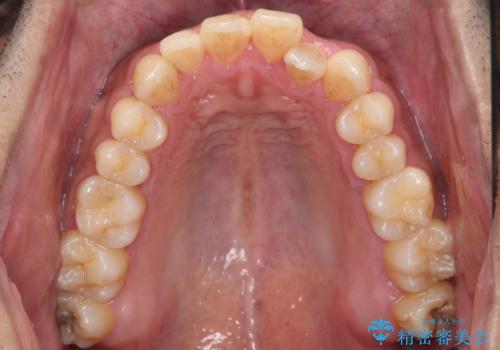

前歯が反対にかんでいる 部分ワイヤーとインビザラインの併用で短期治療

- 前歯の並びを気にして来院。

前歯が一本奥に入っているのを乗り越えるにはワイヤー矯正が治療期間も短く、歯に負担が少なく有利と説明しました。

上はワイヤー部分矯正、下はインビザラインの部分矯正コースを行いました。